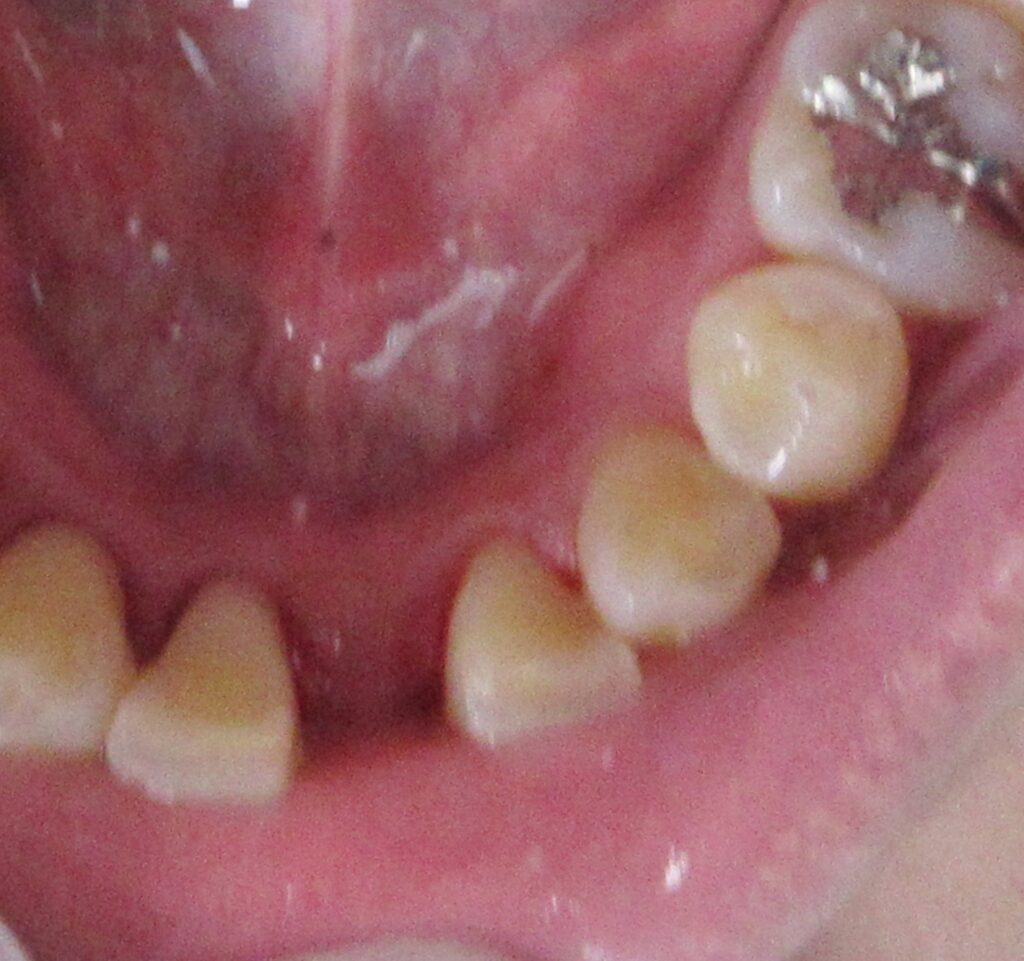

今回の患者様は先天的に欠損している右下1番目、左下1番目にインプラント植立を希望されました。

スペースが狭いため、今回の植立は1本に決まりました。